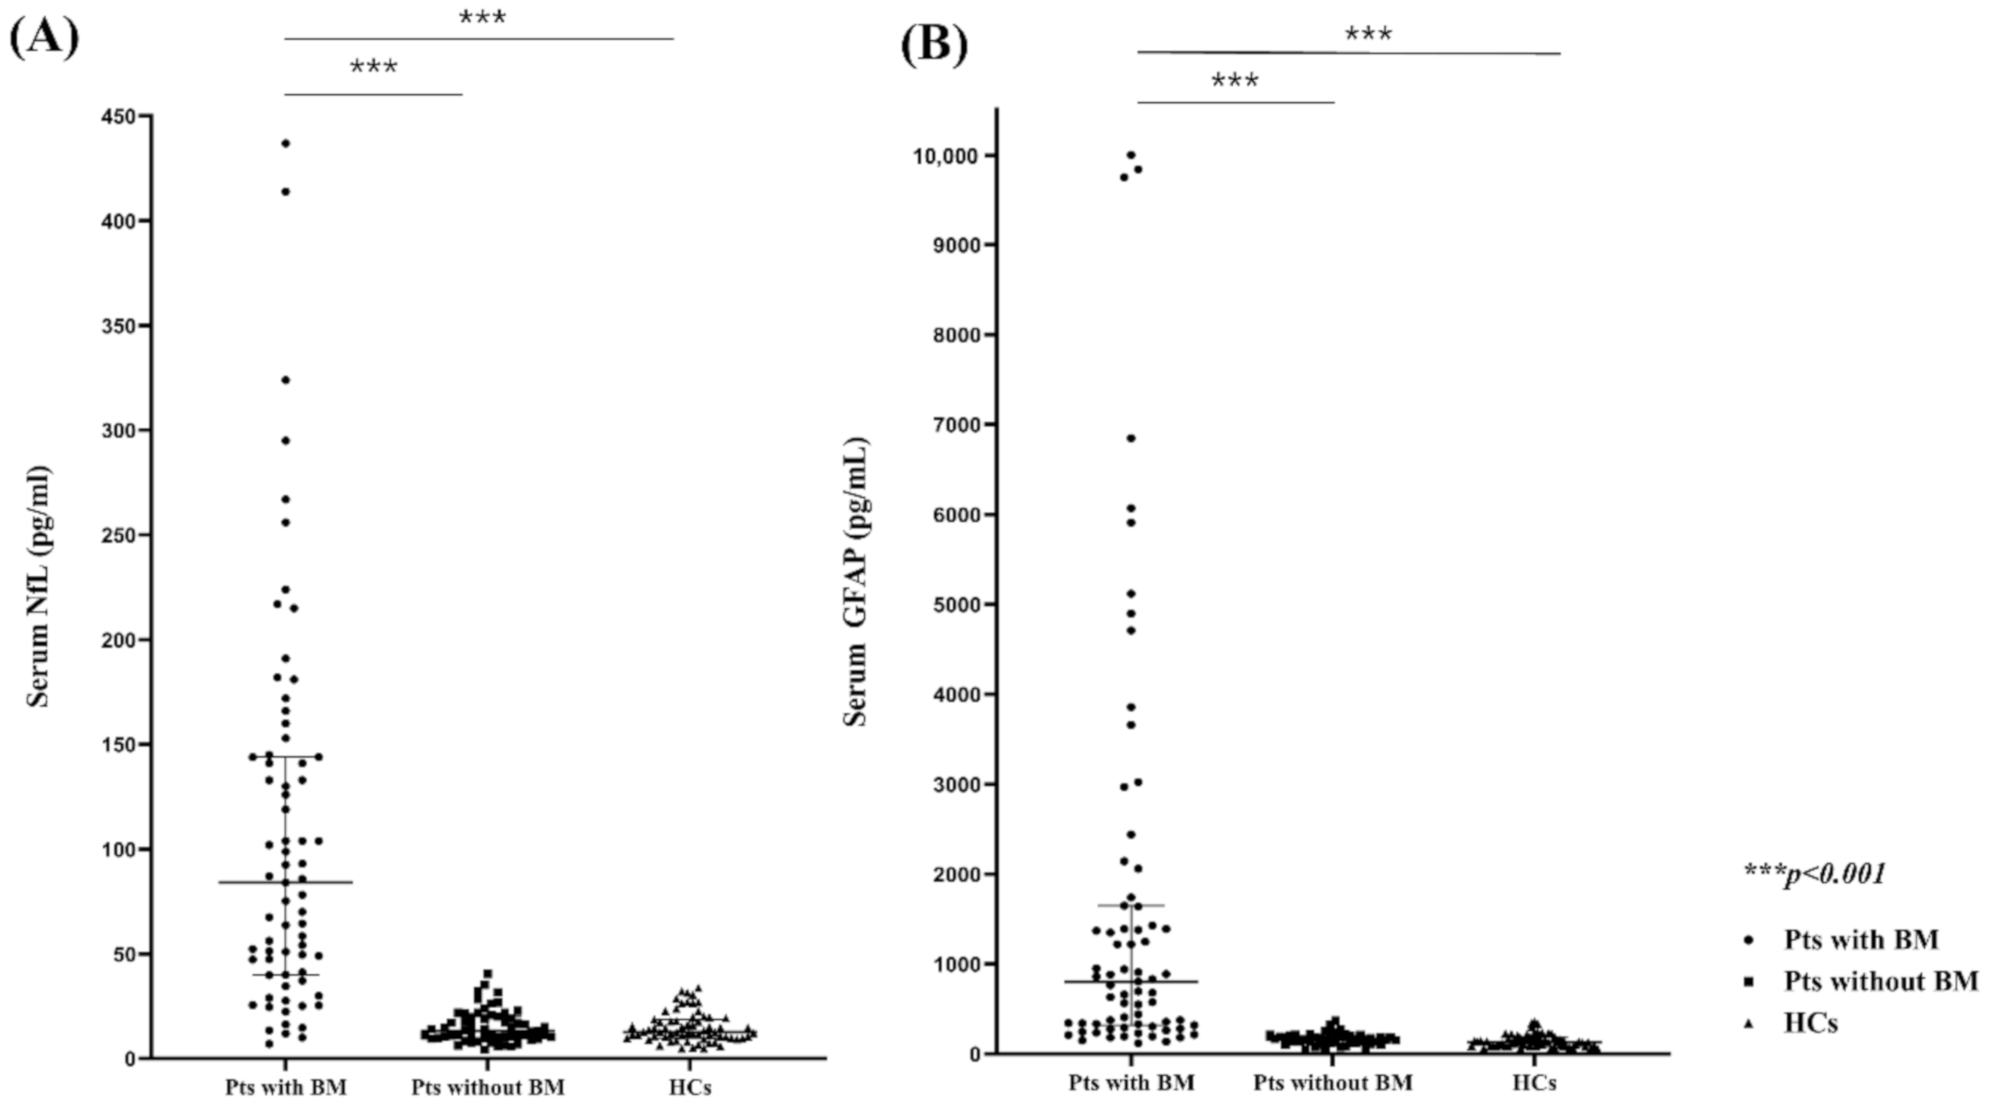

2.2. Comparison of the Serum NfL (sNfl) and GFAP (sGFAP) Levels in Patients with and without BMs and HCs

2.3. sNfL and sGFAP Level as BM Diagnostic Markers